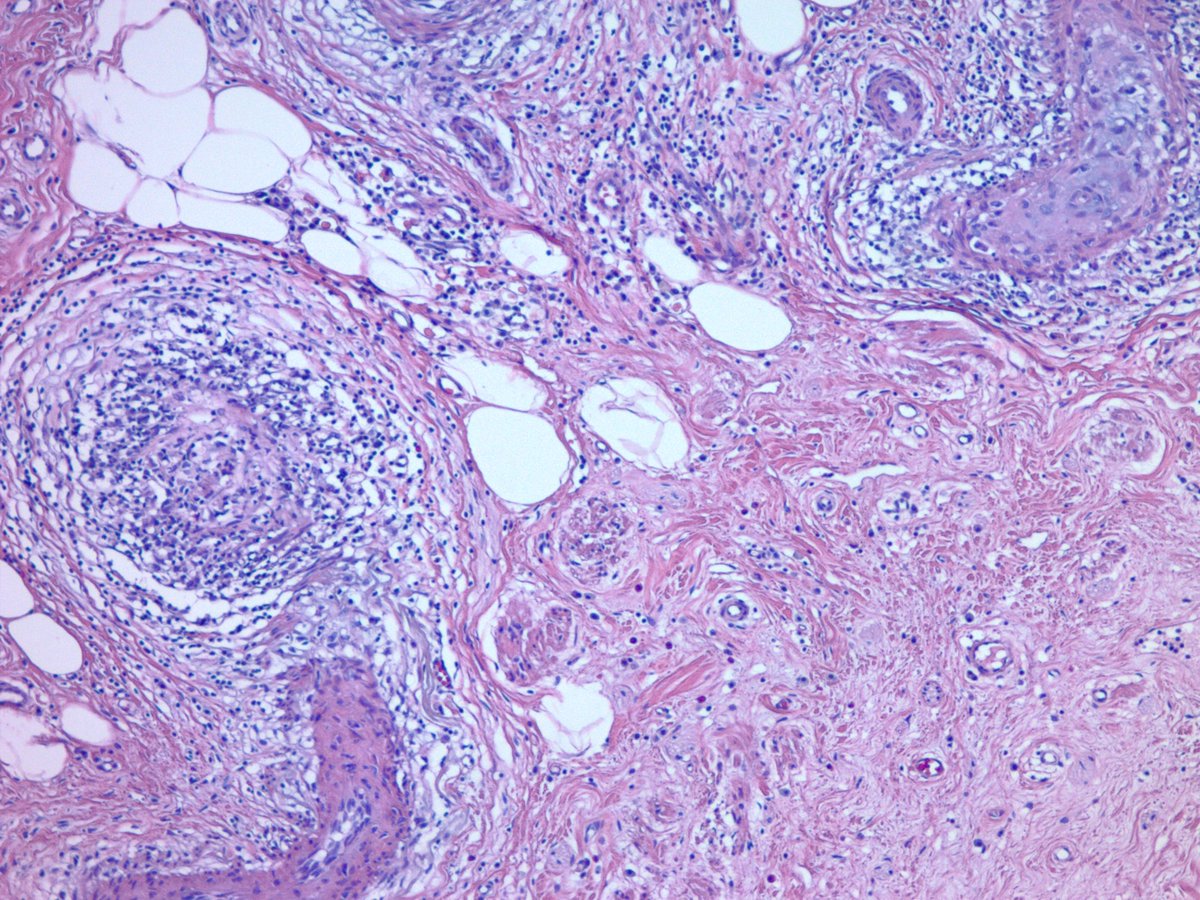

Appendix with lupus vasculitis. Appendectomy for presumed appendicitis. No acute appendicitis seen. Vessels within and outside of the appendix showed these changes with focal fibrinoid necrosis. Clinically and serologically active SLE. #GIpath #pathology

jake_bledsoe's tweet image. Appendix with lupus vasculitis. Appendectomy for presumed appendicitis. No acute appendicitis seen. Vessels within and outside of the appendix showed these changes with focal fibrinoid necrosis. Clinically and serologically active SLE. #GIpath #pathology